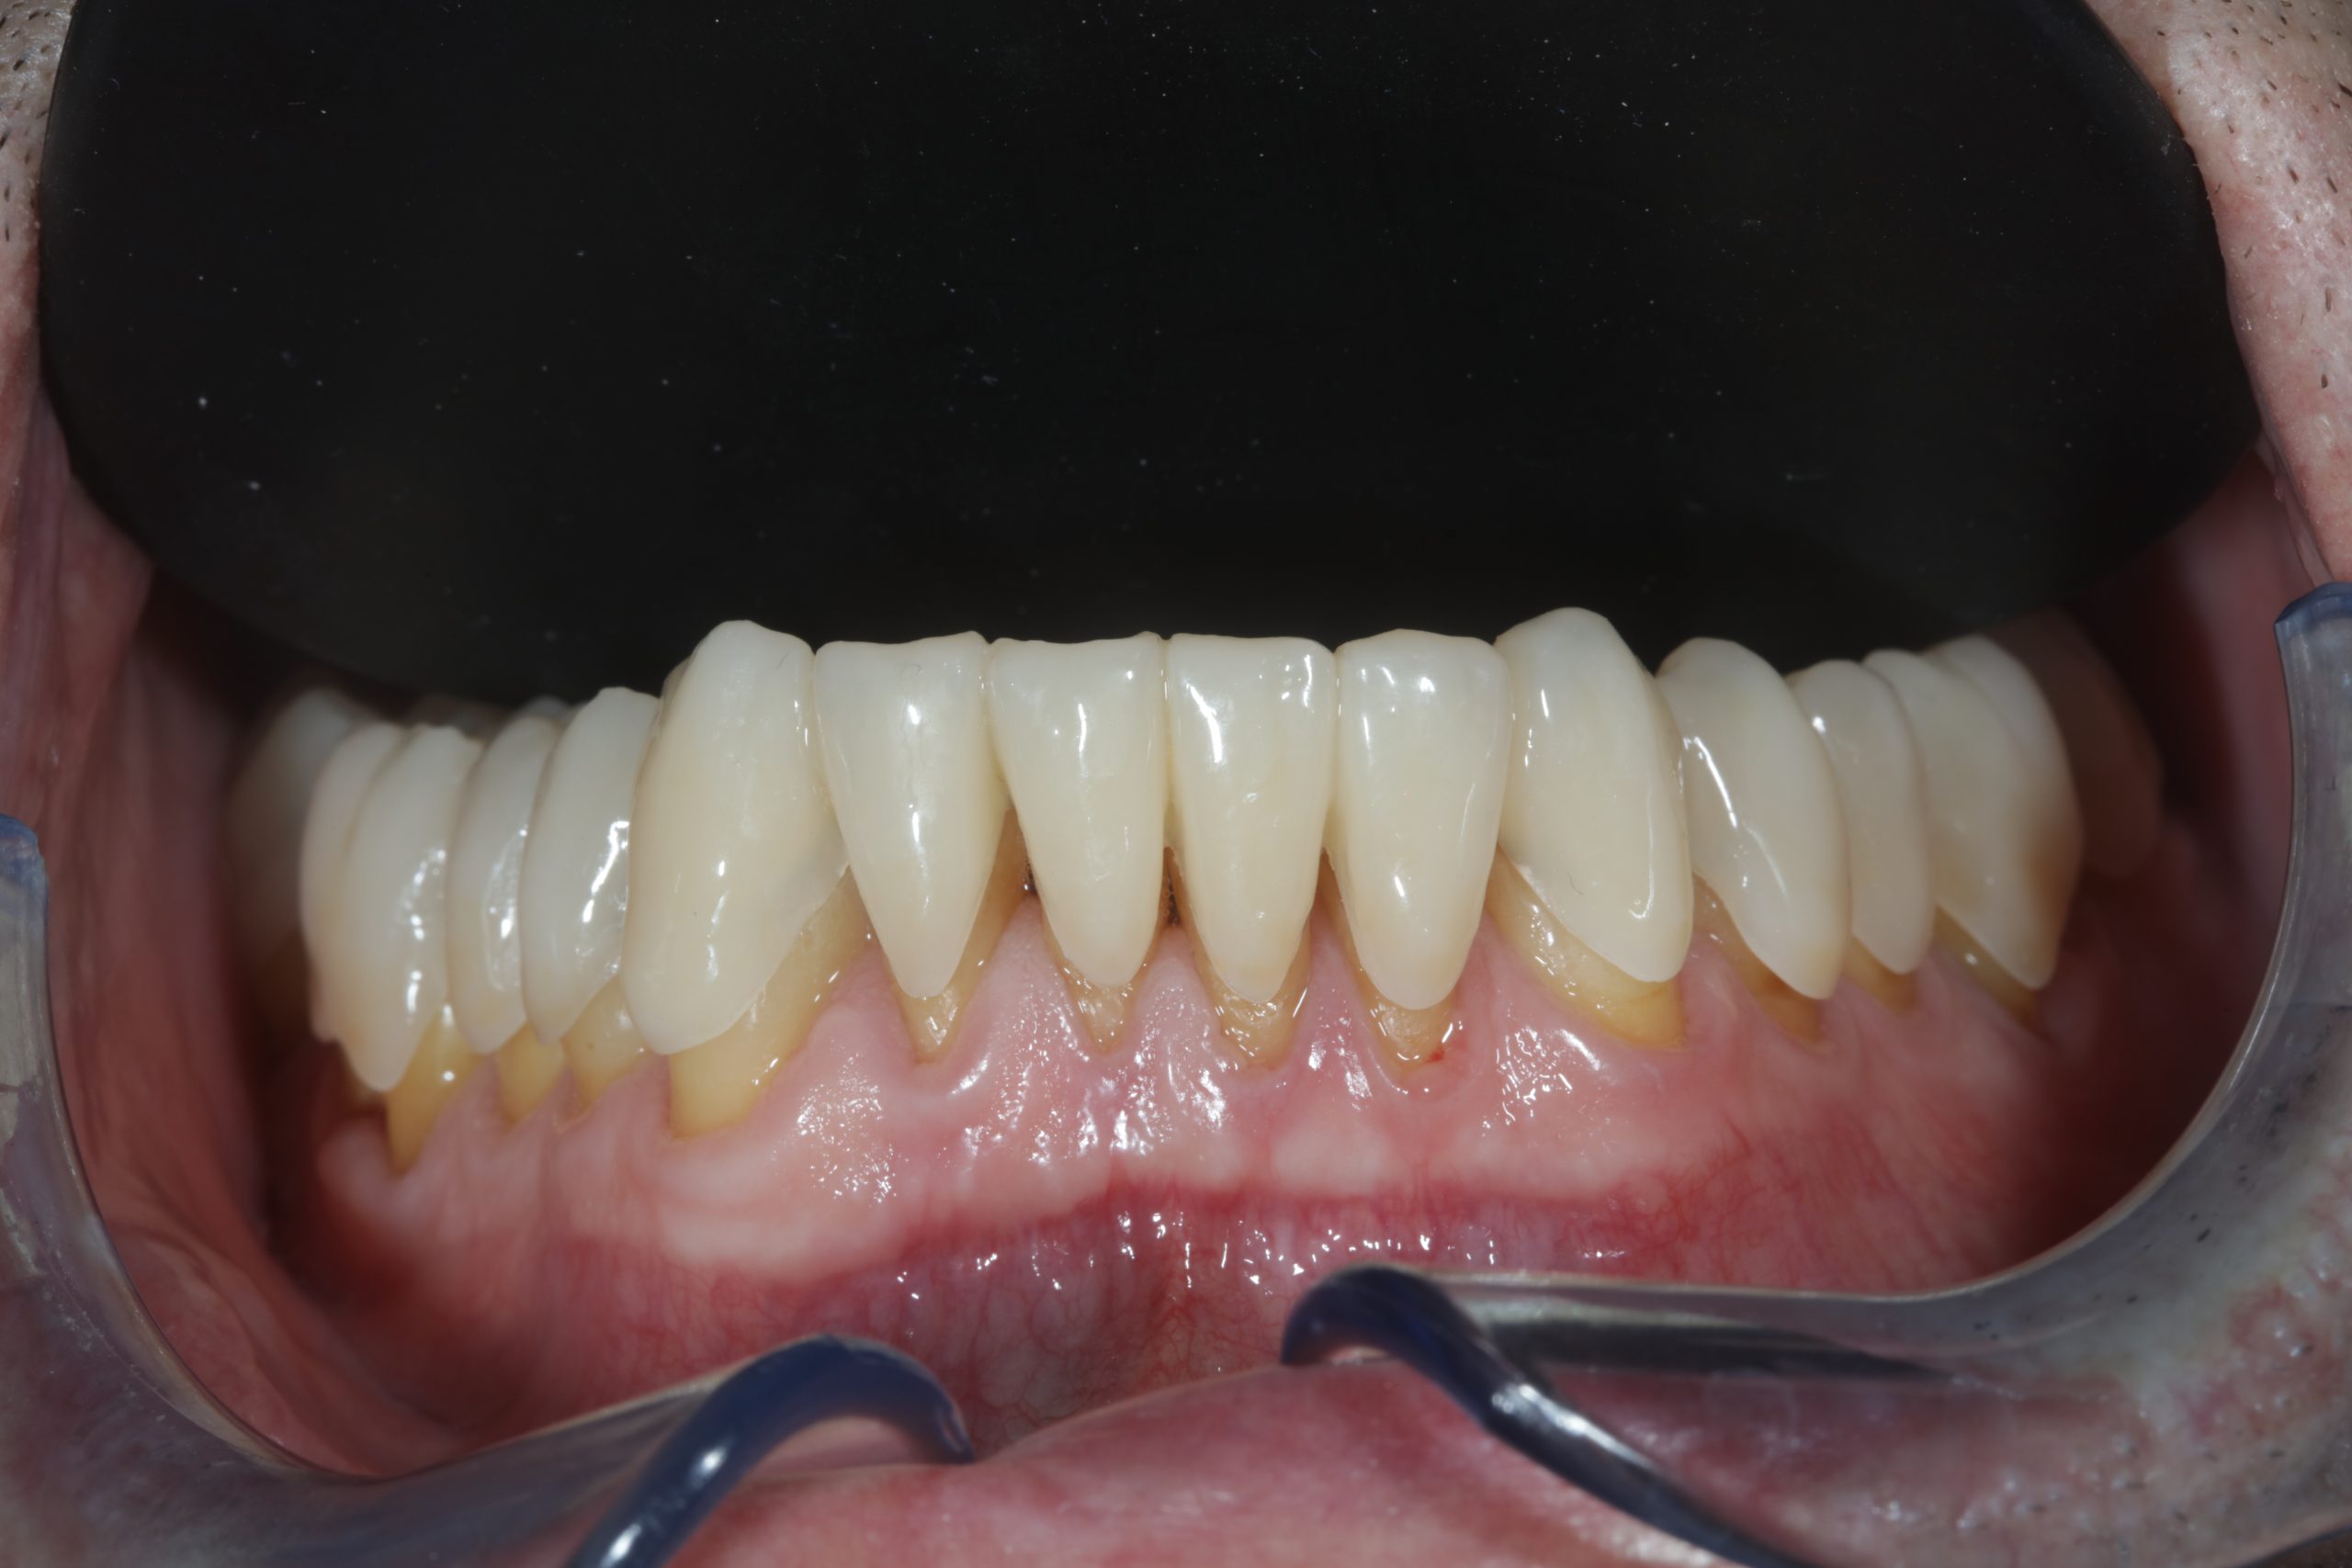

Total upper and lower rehabilitation in zirconia on implants with titanium reinforcement bars

Complete Digital Patient (CDP): the use of guided surgery for implant restoration in total upper and lower rehabilitation with titanium bars and different types of zirconia-ceramic

Full upper and lower rehabilitation with titanium and zirconia bars

Upper and lower prosthetic rehabilitation with titanium bars and translucent zirconia-ceramic structures. The CDP as an aid in communication between the entire team and the patient, who is the focus of the work.